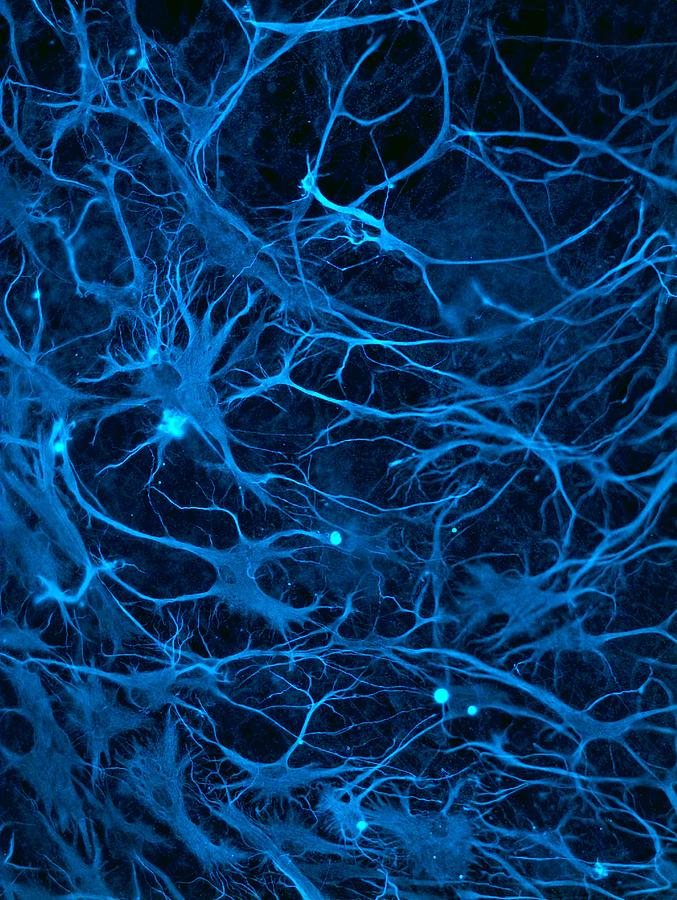

We are a biomedical company developing a new generation of drugs designed to slow or reverse diseases caused by accelerated aging. At the heart of our innovation is a focus on telomeres—the protective caps on our chromosomes that act as the body’s molecular clock. When telomeres shorten too quickly, cells age prematurely, leading to conditions such as idiopathic pulmonary fibrosis, bone marrow failure, diabetes, and neurodegenerative disorders.

Our mission is to restore telomere stability, helping cells regain normal function and extend healthy human lifespan, and in doing so, lower oxidative stress, accumulation od DNA damage, and inflammation. To achieve this, we use a cutting-edge combination of artificial intelligence, comparative genomics, and molecular biology.

Every species on Earth has evolved a unique balance between telomere maintenance and lifespan. Some, like whales or bats, maintain long, stable telomeres for decades, while others lose them quickly. These differences contain vital clues about cellular longevity.

Our proprietary AI platform analyzes telomerase and shelterin gene sequences—the key components responsible for maintaining telomeres—across a wide range of species, including humans. By correlating genetic variations with telomere length and lifespan, the system identifies the most promising genetic patterns for improving telomere stability in human cells.

These insights allow us to model and select the best combinations of telomerase and shelterin genetic variants. We then test them in laboratory models of diseases driven by telomere dysfunction, including diabetes, ataxia-telangiectasia, idiopathic pulmonary fibrosis, and bone marrow failure syndromes. In doing so, we discover the precise molecular mechanisms that restore healthy cellular replication.